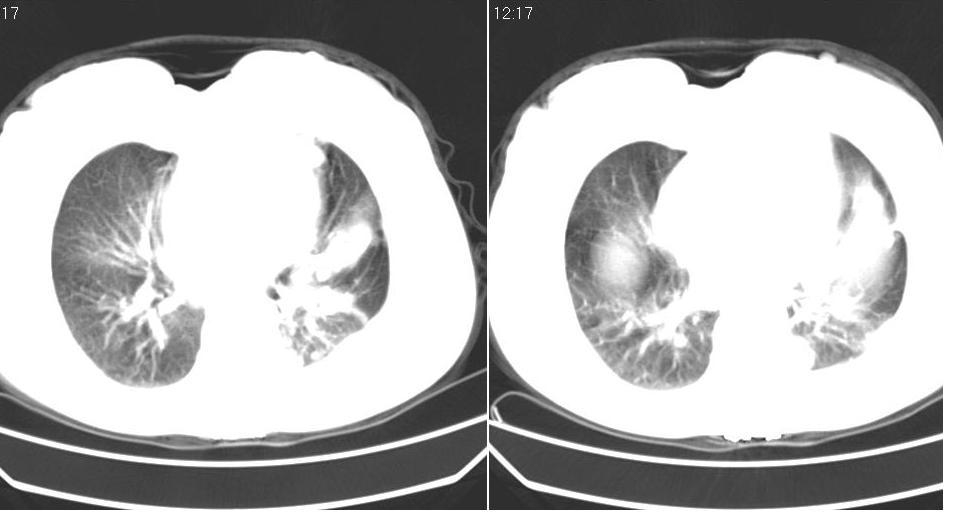

女 59岁,胸背疼,不咳嗽,不咳痰,不发热。

1)考虑左肺下叶背段周围型肺癌并左肺下叶及左侧胸膜转移。2)左侧胸腔积液。3)左冠状动脉钙化。

下叶背段也是结核灶多发区,考虑结核可能性大,建议抽胸水检查,肺癌不排除

考虑结核可能性大,建议胸水检查

1)考虑左肺下叶背段周围型肺癌(腺癌可能性大)并左肺下叶及左侧胸膜转移。2)左侧胸腔积液。3)左冠状动脉钙化。